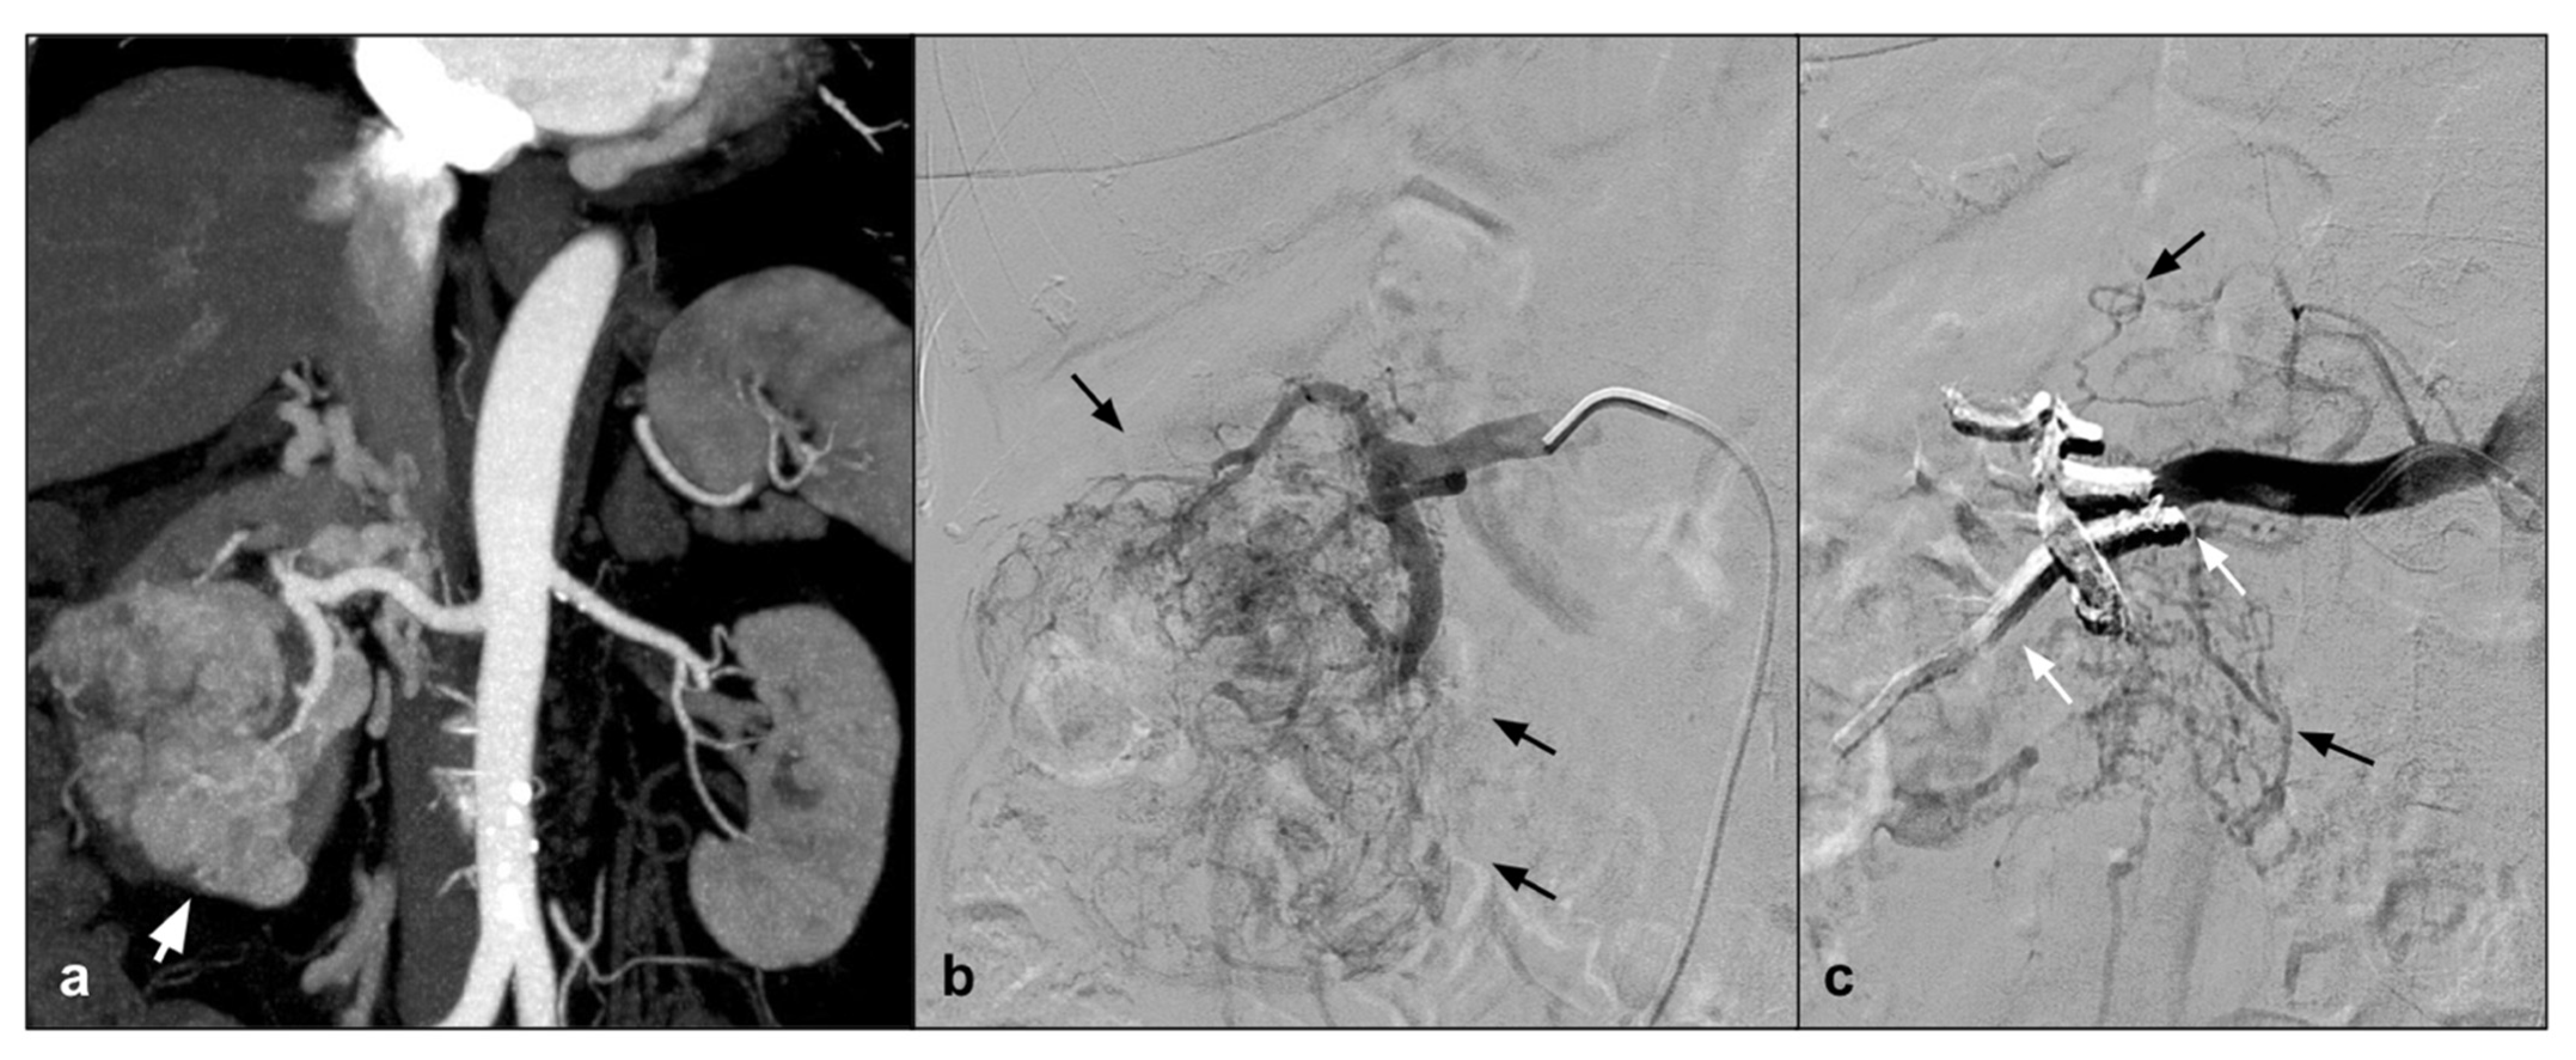

8. Visceral Aneurysms-Pseudoaneurysm

One condition that has been treated with NALEA is splenic aneurysm. A number of papers have recently been published demonstrating the possibility of embolization using NALEA in combination with coils. Both proximal and peripheral splenic aneurysms with different anatomical conformation have been treated in the literature [17,20] (Figure 4).

Figure 4.

(a) Coronal CTA MIP demonstrates post surgical pseudoaneurysm of left gastric artery (white arrows). (b) DSA performed with Simmons 1 catheter at the level of the ostium of the celiac trunk confirms the presence of the pseudoaneurysm (white arrow). (c) DSA performed with microcatheter in the left gastric artery highlights a saccular dilation (white arrow) of the left gastric artery with regular patency of the efferent vessel (black arrow). (d) Post-procedure DSA control demonstrates complete exclusion of the treated PSA (asterisk) with an Onyx 18 cast completely occupying the malacic vessel performing an “endovascular ligature technique” (white arrow).

A second solid experience was published by Urbano et al. in 2017 [65], who performed in 22 consecutive patients and 25 lesions for symptomatic AMLs or AMLs > 4 cm. Mean AML size in this study was 7 cm. In this study, the peculiarity is that EVOH copolymer was the only embolic agent used. A postembolization syndrome was scheduled in 18.5% of patients, maybe because, when using only Onyx, a large quantity of EVOH was injected. Also for Urbano et al., AML embolization with EVOH copolymer is feasible, safe, and effective (Figure 5).

Figure 5.

(a) Coronal CTA MIP highlights a large angiomyolipoma of the right kidney lower third (white arrow). (b) DSA performed with a direct injection in the right renal artery confirms the lesion with an abnormal arterial vascularization (black arrows). (c) A post procedure DSA check demonstrates the presence of the Squid 34 cast which completely occludes the tributary arteries of the lesion (white arrows) and preservation of the healthy renal parenchyma (black arrows).